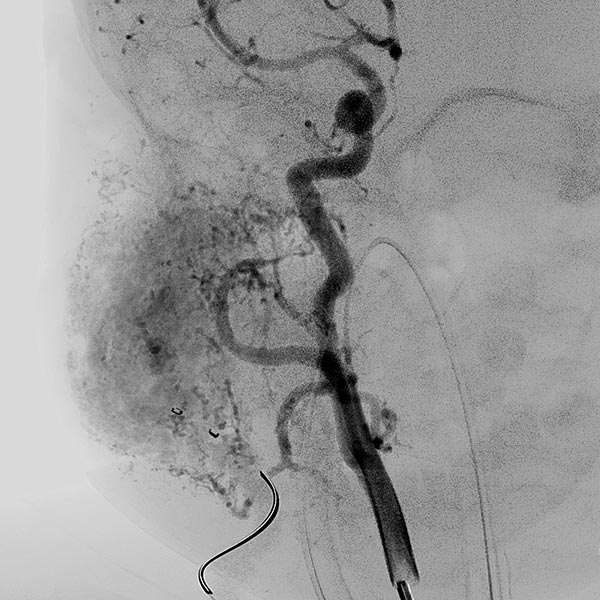

Digital subtraction angiography (DSA) after injection into the right common carotid artery shows the infantile hemangioma mainly supplied from the external carotid artery, as expected.

Digital subtraction angiography (DSA): After insertion of a 4F diagnostic catheter transarterially into the external carotid artery, selective advancement of a microcatheter into the maxillary artery. The infantile hemangioma presents as typical contrast pooling (“tumor blush”). The transvenously inserted balloon blocks the venous outflow and is clearly visible. Embolization was then carried out with particles of 150 micron size and without unintended venous outflow.